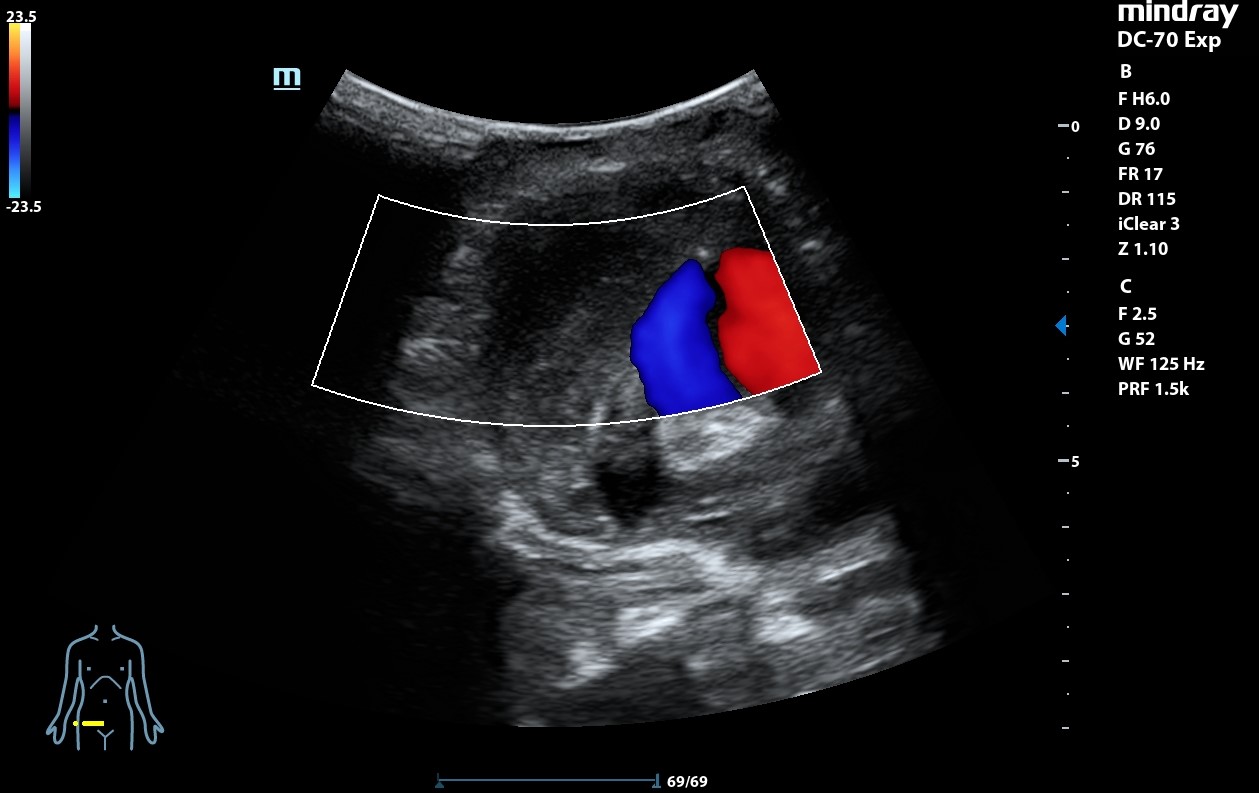

Ecografía clínica: arteria femoral dilatada con material hipoecoico heterogéneo en su pared lateral con un diámetro de 5,85 x 5,88 cm. Dilatación de aorta infrarrenal de 5,1 cm.

Diagnóstico: Aneurisma de arteria femoral derecha. aneurisma de aorta.

Informe TAC aorta: Dilatación aneurismática de la aorta abdominal infrarenal, de 5 x 5 x 6,4 cm, sin signos de complicación. Imagen sacular de la arteria femoral derecha compatible con pseudoaneurima, que asocia hematoma circundante, de al menos 8,6 x 7,8 x 8,8 cm con áreas de extravasación de contraste en fase arterial, sugestivas de sangrado activo de alto débito.